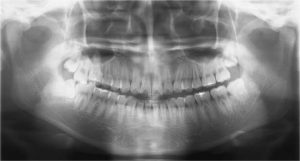

こちらは全部の歯を撮影する機械です。

やり方はまず、青い所に顎を乗せ、透明の器具を前歯で噛みます。

そして頭の横の白い機械が、頭の周りをぐるっと一周するので、

周り終わるまで正面を見てお待ちください。

このようなお口全体の写真が撮れます。